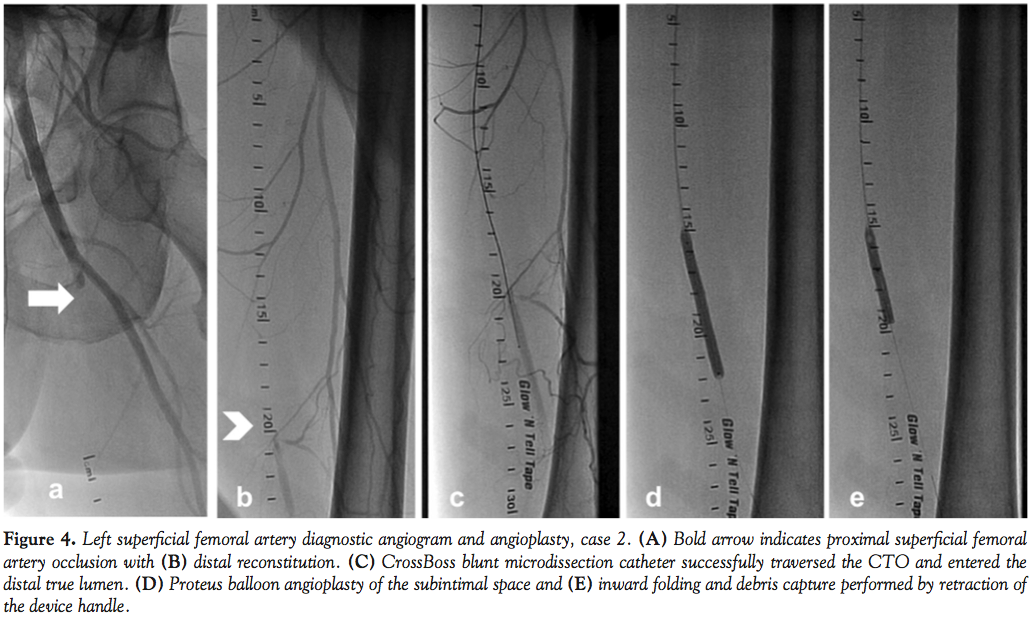

Case 2. A 59-year-old hypertensive man with severe PAD and life-style limiting, bilateral lower-extremity claudication was referred for diagnostic angiography and intervention. ABI on right and left lower extremities were 0.62 and 0.50, respectively. Diagnostic angiography revealed an ostial occlusion of the left SFA with distal reconstitution and triple-vessel infra-popliteal runoff (Figures 4A and 4B). We accessed this lesion with a 6 Fr sheath through a contralateral femoral arterial approach. We crossed the proximal cap of the CTO using a CrossBoss™ (BridgePoint Medical) blunt microdissection catheter, which successfully traversed the CTO and entered the distal true lumen. A 5.0 x 60 mm Proteus balloon was delivered and the lesions dilated. The balloon was then deflated to 2 atm and inward folding and debris capture were performed by retraction of the device handle, following which the balloon was completely deflated and removed (Figures 4C-4E). The evacuated balloon was unfolded and debris stained with hematoxylin-eosin on a filter (Figure 3B). Angiogram performed post-Proteus angioplasty revealed good angiographic result with 40% residual stenosis, which was treated with two overlapping 6.0 x 150 mm self-expanding nitinol stent implantations. The stented segments were postdilated with an excellent final angiographic result.